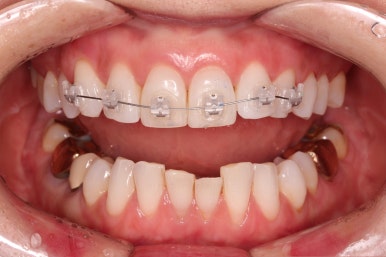

적절하게 치간삭제를 일부 동반하여 빠른 시일 내에 가지런하게 해드리고 마무리를 했습니다.

연산동부분교정 치료 기간이 3개월 밖에 되지 않아 중간 자료사진이 없네요.

환자분이 원하시는 만큼 가지런해졌고, 부가적으로 생길 수 있는 부분들도 수용 가능한 선에서 잘 마무리가 되었습니다.

3개월이라는 빠른 기간 내에(심미보철 보다 약간만 더 긴 시간) 치아의 손상없이 마무리를 잘 했습니다.

물론 중간에 장치를 부착한 기간동안은 심미적으로 부담스러우셨겠지만요.

아래 앞니는 부분교정까지는 원하지 않으셔서 약간 다듬어 드리고 종료했습니다.